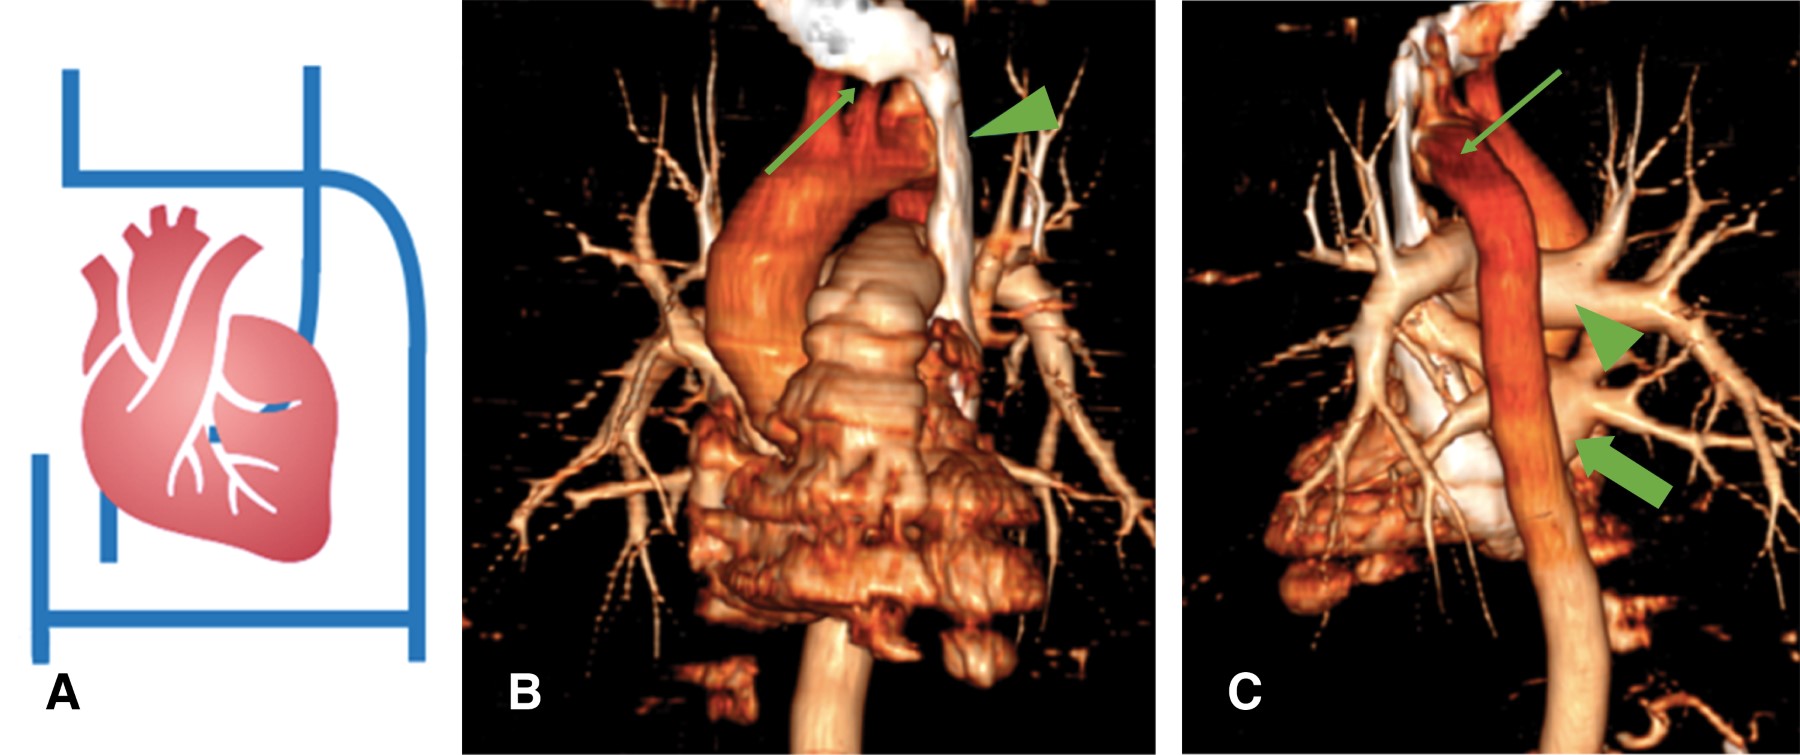

Pacemaker implantation through the persistent left superior vena cava due to the absence of the right superior vena cava. Report of a case

Introduction: the persistence of the left superior vena cava (PLSVC) has a prevalence of 0.21% in the general population. Case presentation: 67-year-old male diagnosed with third-degree AV block, requiring pacemaker placement. However, due to the absence of a right superior vena cava, corroborated by CT angiography, a definitive pacemaker was placed through a persistent left superior vena cava. Conclusion: the persistence of the left superior vena cava (PLSVC) is the most common thoracic venous anomaly. It can cause a number of clinically significant symptoms, even in a heart with normal anatomy. Pacemaker placement makes electrode fixation difficult due to tortuous travel.

Figure 4